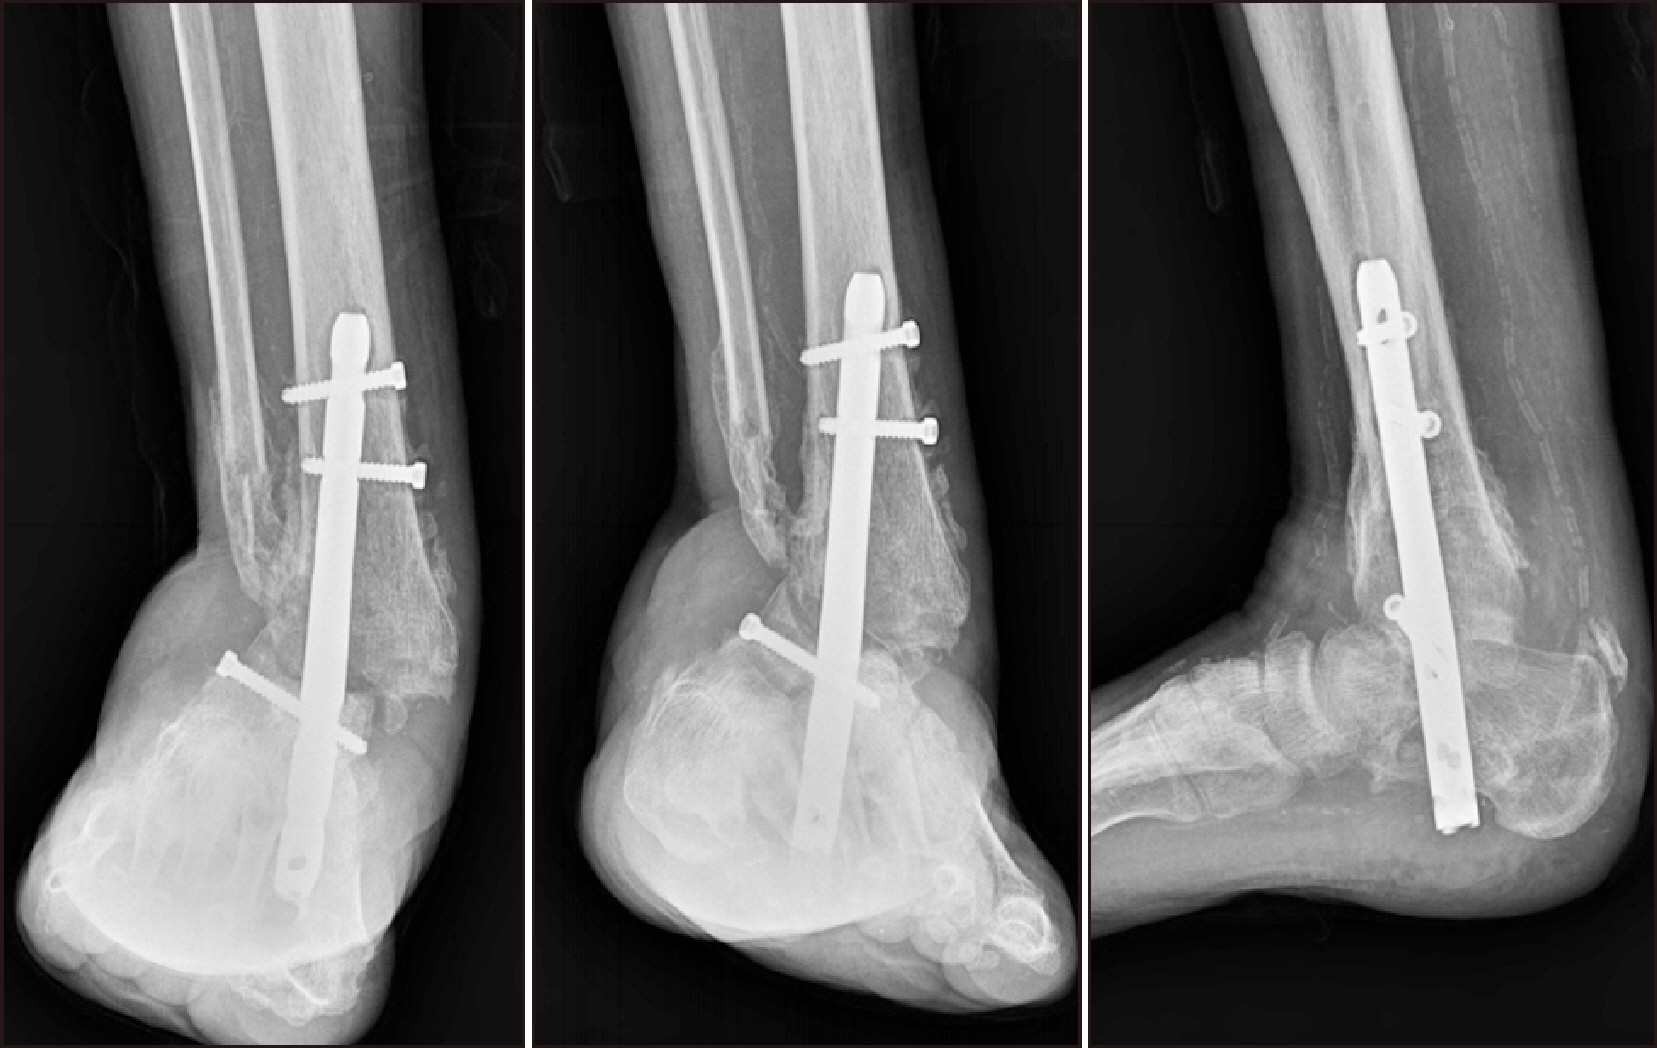

Comprehensive Management of Presumed Underlying Charcot Arthropathy with a Subsequent Traumatic Ankle Fracture in a Patient with Diabetes Mellitus, End-Stage Renal Disease: A Case Report

Charcot neuroarthropathy (CN), also known as Charcot arthropathy, is a complex, progressive disorder primarily affecting the foot and ankle. This case report describes a multifaceted management strategy for a 54-year-old male with diabetes mellitus, end-stage renal disease, and presumed underlying Charcot arthropathy who experienced a traumatic ankle fracture. The initial surgical plans were delayed because of systemic infection indicators, including elevated C-reactive protein levels and high fever. The patient underwent multiple surgical interventions and faced challenges, including metal failure, implant-associated infection, and tibiotalar joint dislocation. A multidisciplinary approach involving orthopedic surgeons, nephrologists, and endocrinologists was crucial for managing the case effectively. In particular, the patient declined a below-knee amputation and opted for comprehensive surgical intervention, resulting in improved functionality at the latest follow-up. This case highlights the complexities of managing CN in patients with multiple comorbidities and emphasizes the need for a nuanced, patient-centered approach.